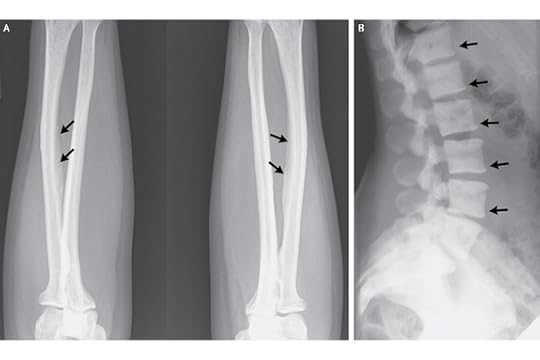

Source: HealthyChildren.orgWhat about more severe toxicity? Well, it turns out that not only your teeth are affected by fluoride, but your bones. In some areas of the world, particularly where the fluoride levels in the water are high due to contaminated water supplies or geological sources, fluorosis can occur.

Source: HealthyChildren.orgWhat about more severe toxicity? Well, it turns out that not only your teeth are affected by fluoride, but your bones. In some areas of the world, particularly where the fluoride levels in the water are high due to contaminated water supplies or geological sources, fluorosis can occur.

Chronic fluorosis, which is from consuming too much fluoride over time, can result in denser but brittle bones, calcified ligaments, stiffness and joint pain.

The arrows are pointing to excessive calcium deposits on the forearms and spine. Source: NEJMAcute fluoride toxicity can occur in areas after industrial explosions or accidents (like from a hydrofluoric acid spill), or more commonly by ingestion of too way much fluoride-containing dental products. Symptoms can include nausea, vomiting and diarrhea (the trifecta of GI distress! In doctor's notes, we write that as N/V/D, in case you were wondering), kidney damage, heart damage, and possibly even death.

The arrows are pointing to excessive calcium deposits on the forearms and spine. Source: NEJMAcute fluoride toxicity can occur in areas after industrial explosions or accidents (like from a hydrofluoric acid spill), or more commonly by ingestion of too way much fluoride-containing dental products. Symptoms can include nausea, vomiting and diarrhea (the trifecta of GI distress! In doctor's notes, we write that as N/V/D, in case you were wondering), kidney damage, heart damage, and possibly even death.

And guess what? You can get it from tea, too. Tea plants tend to accumulate fluoride from the soil. See those x-rays up there? They were from a woman who drank >100 tea bags worth of tea every day for 17 years (read here for the New England Journal of Medicine article.)

Source: HealthyChildren.orgWhat about more severe toxicity? Well, it turns out that not only your teeth are affected by fluoride, but your bones. In some areas of the world, particularly where the fluoride levels in the water are high due to contaminated water supplies or geological sources, fluorosis can occur.

Source: HealthyChildren.orgWhat about more severe toxicity? Well, it turns out that not only your teeth are affected by fluoride, but your bones. In some areas of the world, particularly where the fluoride levels in the water are high due to contaminated water supplies or geological sources, fluorosis can occur.Chronic fluorosis, which is from consuming too much fluoride over time, can result in denser but brittle bones, calcified ligaments, stiffness and joint pain.

The arrows are pointing to excessive calcium deposits on the forearms and spine. Source: NEJMAcute fluoride toxicity can occur in areas after industrial explosions or accidents (like from a hydrofluoric acid spill), or more commonly by ingestion of too way much fluoride-containing dental products. Symptoms can include nausea, vomiting and diarrhea (the trifecta of GI distress! In doctor's notes, we write that as N/V/D, in case you were wondering), kidney damage, heart damage, and possibly even death.

The arrows are pointing to excessive calcium deposits on the forearms and spine. Source: NEJMAcute fluoride toxicity can occur in areas after industrial explosions or accidents (like from a hydrofluoric acid spill), or more commonly by ingestion of too way much fluoride-containing dental products. Symptoms can include nausea, vomiting and diarrhea (the trifecta of GI distress! In doctor's notes, we write that as N/V/D, in case you were wondering), kidney damage, heart damage, and possibly even death. And guess what? You can get it from tea, too. Tea plants tend to accumulate fluoride from the soil. See those x-rays up there? They were from a woman who drank >100 tea bags worth of tea every day for 17 years (read here for the New England Journal of Medicine article.)